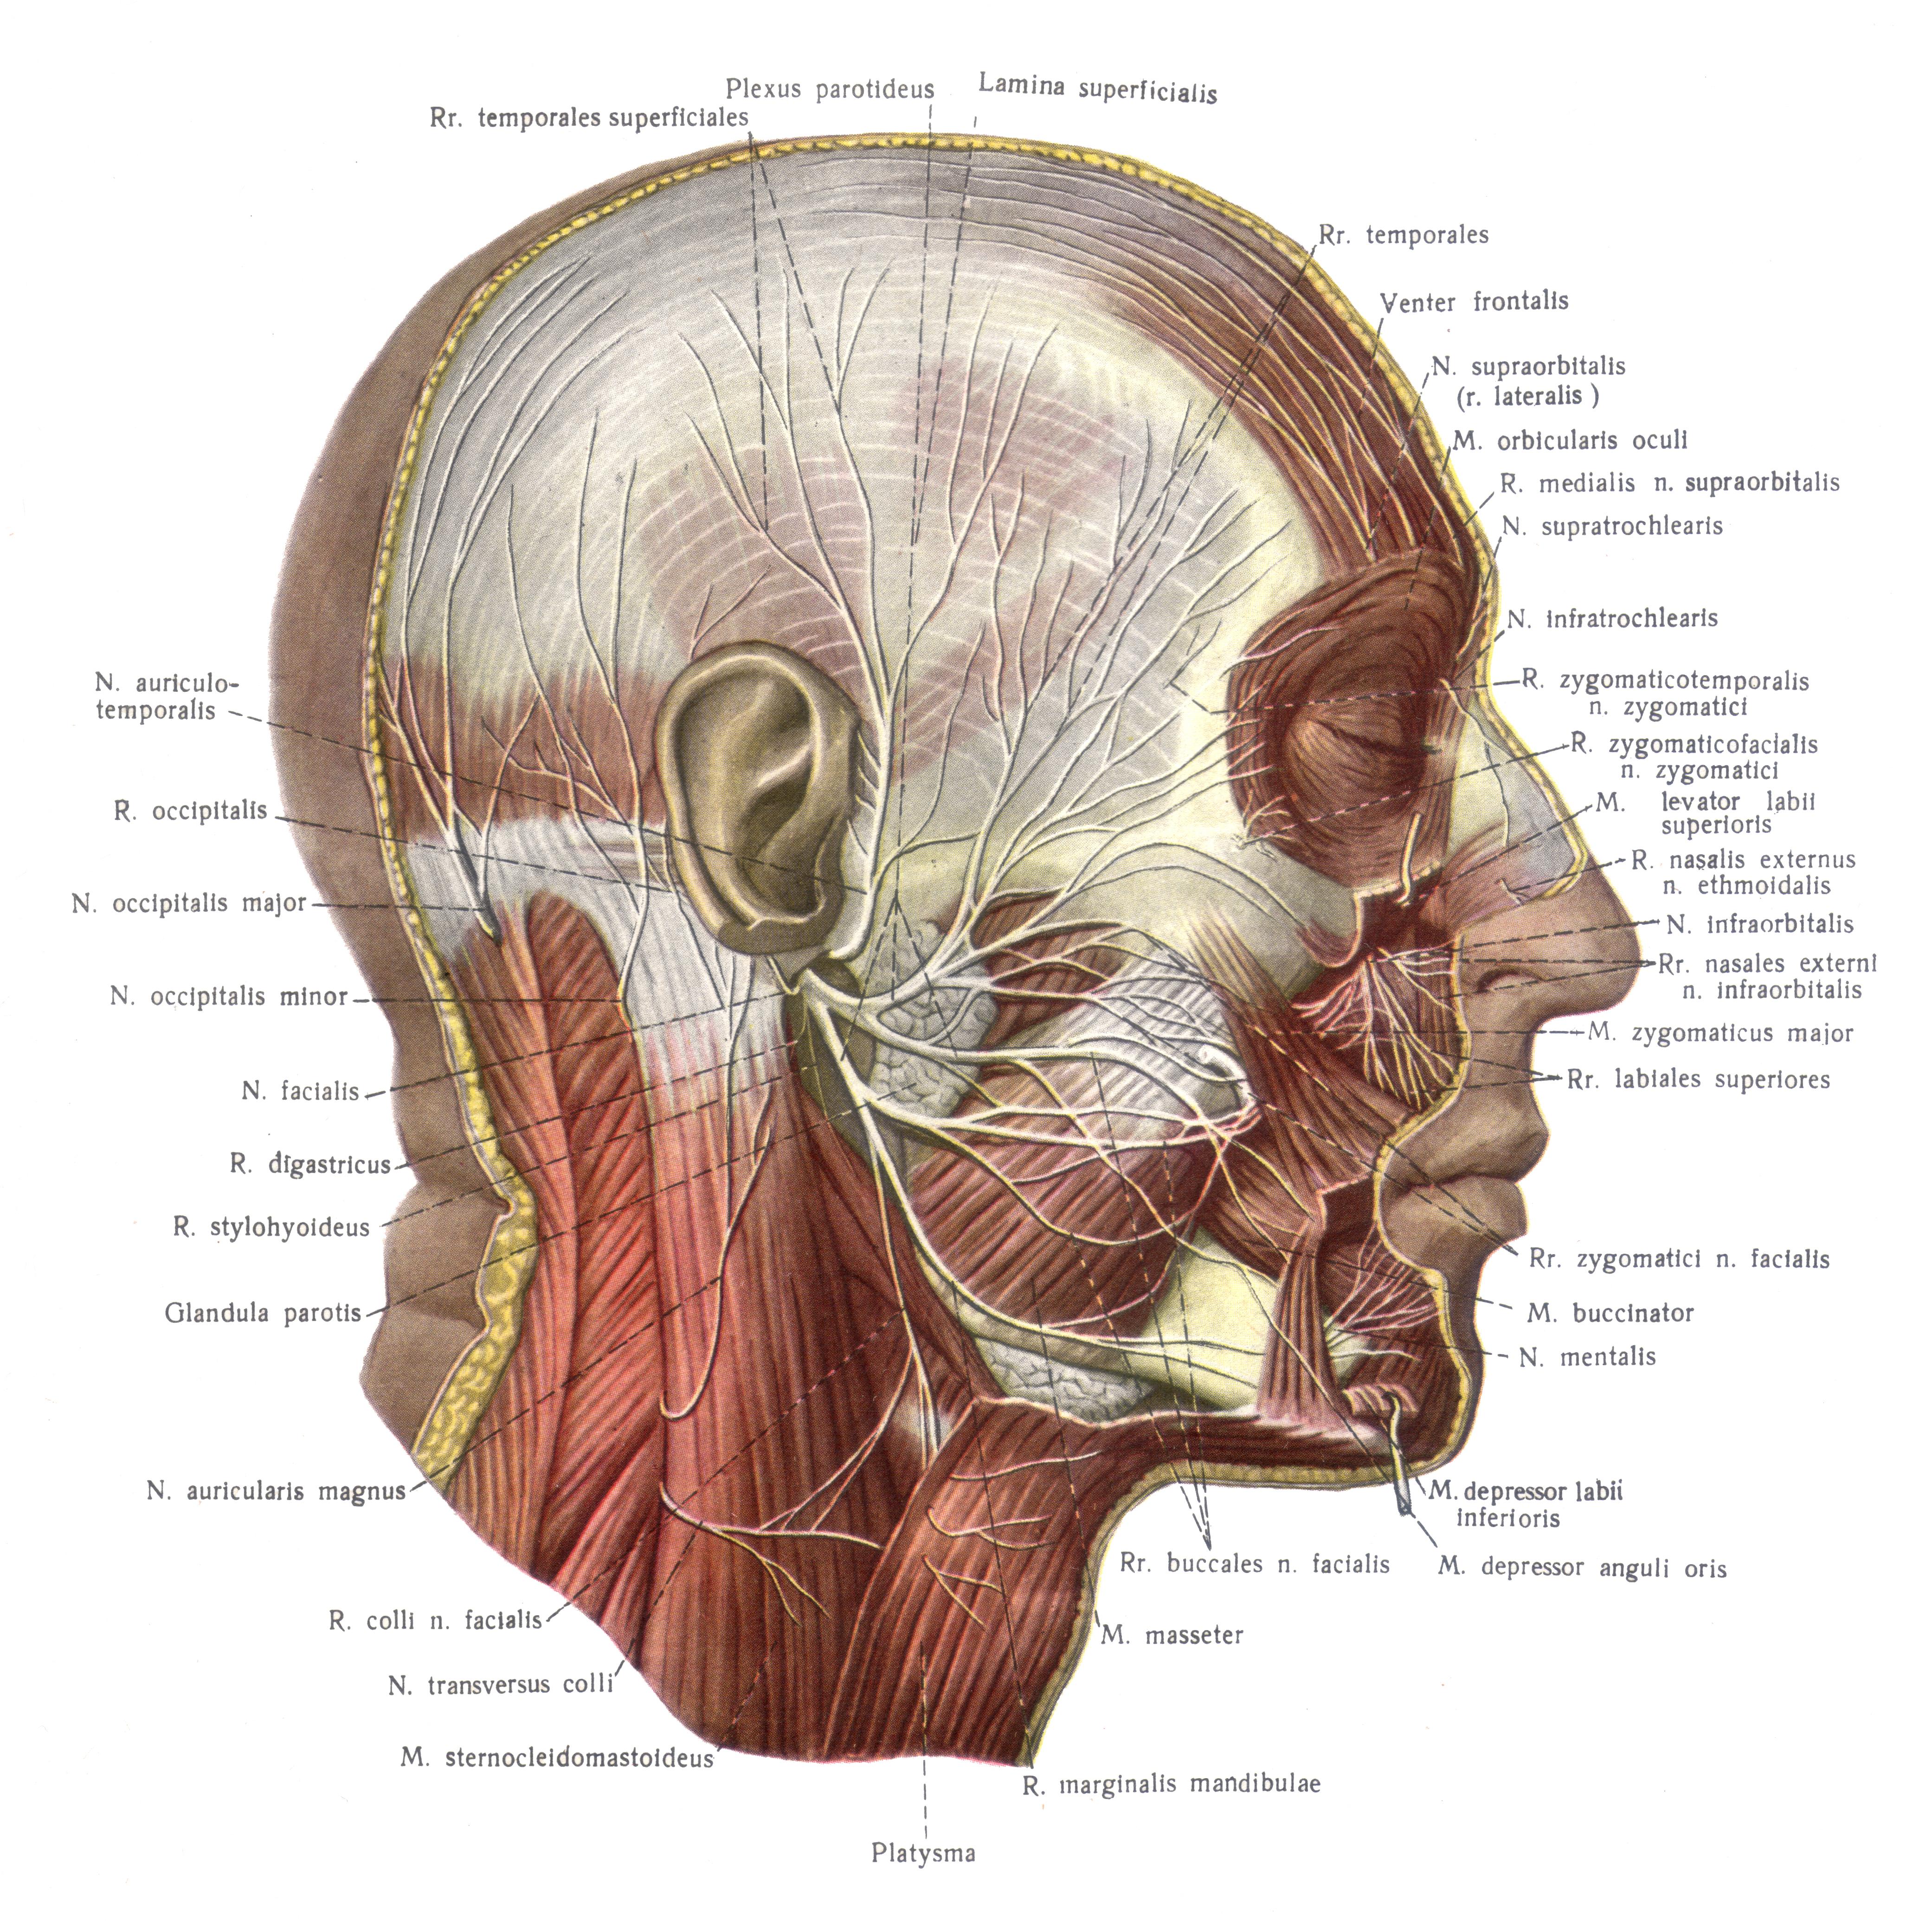

Анатомия сосцевидного отростка